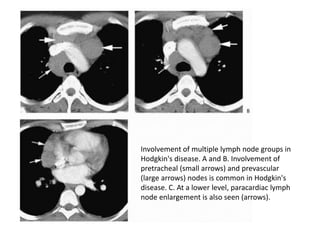

Involvement of multiple lymph node groups in

Hodgkin's disease. A and B. Involvement of

pretracheal (small arrows) and prevascular

(large arrows) nodes is common in Hodgkin's

disease. C. At a lower level, paracardiac lymph

node enlargement is also seen (arrows).